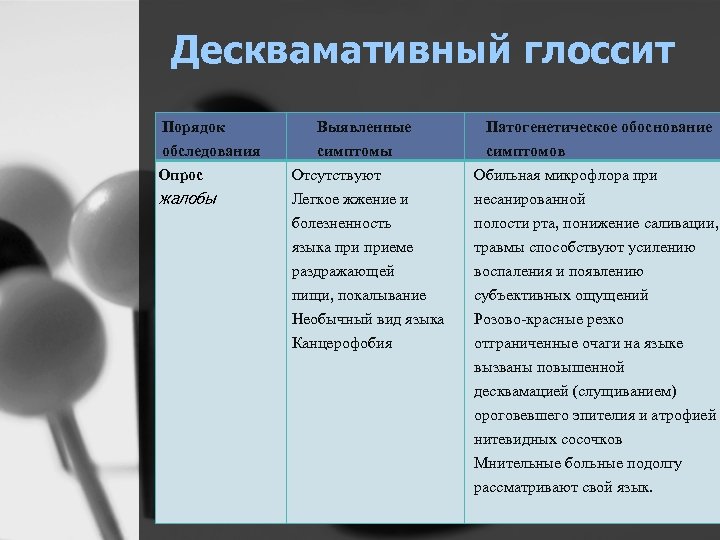

Десквамативный глоссит Порядок обследования Опрос жалобы Выявленные симптомы Отсутствуют Легкое жжение и болезненность языка приеме раздражающей Патогенетическое обоснование симптомов Обильная микрофлора при несанированной полости рта, понижение саливации, травмы способствуют усилению воспаления и появлению пищи, покалывание Необычный вид языка Канцерофобия субъективных ощущений Розово-красные резко отграниченные очаги на языке вызваны повышенной десквамацией (слущиванием) ороговевшего эпителия и атрофией нитевидных сосочков Мнительные больные подолгу рассматривают свой язык.